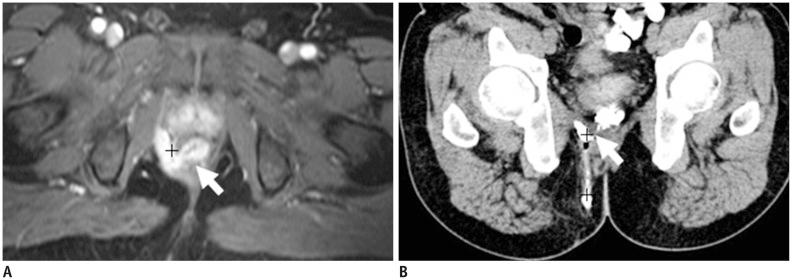

Imaging of anal fistulas: comparison of computed tomographic fistulography and magnetic resonance imaging.

The primary importance of magnetic resonance (MR) imaging in evaluating anal fistulas lies in its ability to demonstrate hidden areas of sepsis and secondary extensions in patients with fistula in ano. MR imaging is relatively expensive, so there are many healthcare systems worldwide where access to MR imaging remains restricted. Until recently, computed tomography (CT) has played a limited role in imaging fistula in ano, largely owing to its poor resolution of soft tissue. In this article, the different imaging features of the CT and MRI are compared to demonstrate the relative accuracy of CT fistulography for the preoperative assessment of fistula in ano. CT fistulography and MR imaging have their own advantages for preoperative evaluation of perianal fistula, and can be applied to complement one another when necessary.